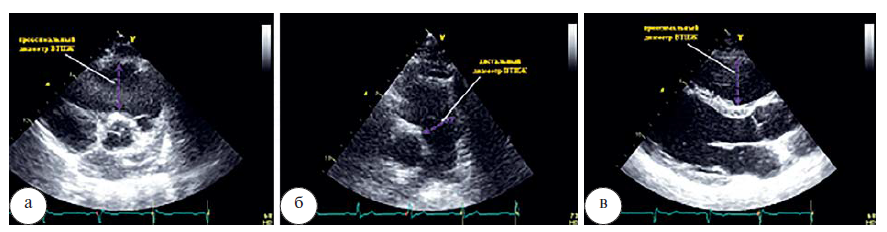

Размер ПЖ может быть получен из верхушечного четырехкамерного сечения в конце диастолы. Размеры ПЖ сильно зависят от поворотов датчика, что приводит к недооценке его параметров. Важно попытаться найти оптимальную точку в 4-камерном сечении для получения «сфокусированного сечения на ПЖ» (рис. 1). По рекомендациям EACVI (2017) диаметр более 42 мм на базальном уровне и более 36 мм в средней трети рассматривается как дилатация ПЖ.

Рис. 1. Измерение диаметра ПЖ на базальном и срединном уровне в «сфокусированном сечении на ПЖ»

Проксимальный диаметр выходного тракта (ВТПЖ) должен быть измерен в продольном парастернальном сечении по длинной и короткой оси в конце диастолы. Верхняя граница составляет 36 мм (рис. 2 а, б). Дистальный диаметр ВТПЖ, измеренный в конце диастолы на уровне пульмонального клапана должен составлять менее 28 мм (рис. 2 в).

Рис. 2. Измерение проксимального диаметра выходного тракта ПЖ в парастернальном сечении по длинной оси (а), по короткой оси (б), дистального диаметра выходного тракта ПЖ в парастернальном сечении на уровне пульмонального клапана (в)